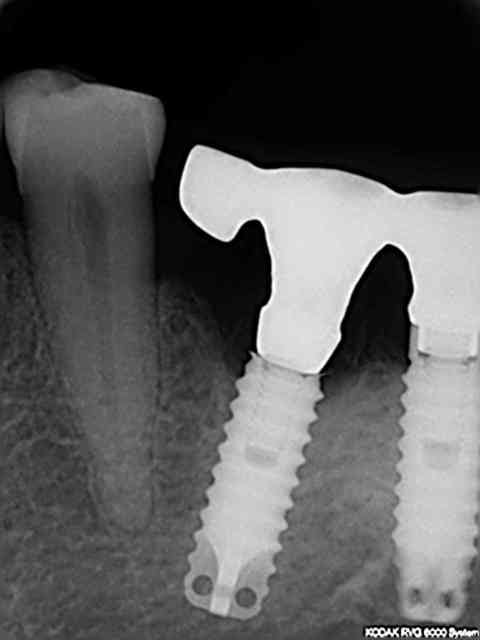

en ragardant le sujet vis cassée je vous donne des nouvelles de l'implant col cassé deux ans après et du petit bricolage généré dessus.

nous avons réalisé une armature sur la barre avec un petit fraisage et scellé le tout.

comme j'ai la chance que les patients fassent le suivi

rvg en 2011

pseudo réossification autour de mon bricolage si on fait attention faut dire que c'est un beau cône morse (!)

Euh je ne veux pas être négatif mais je dirai plutôt une cratérisation établie; ton os arrivait à la spire distal n°10 (à l'origine) maintenant il est bien en dessous :-(

pourquoi penses tu que je parle de "pseudo" réossification et de cone morse : aucune étanchéité autour du bricolage qui présente encore moins d'étanchéité qu'un connectique à plat

les contraintes que montraient Haig sont bien toujours présentes même si soulagées par le fait que l'on ait "acastillé" l'autre coté .

il s'agit d'un sauvetage la corticale en linguale est toujours présente mais poche en vestibulaire car l'axe de cet implant n'est pas non plus idéal en vestibulo lingual comme mésio distal ya pas de raison:-))